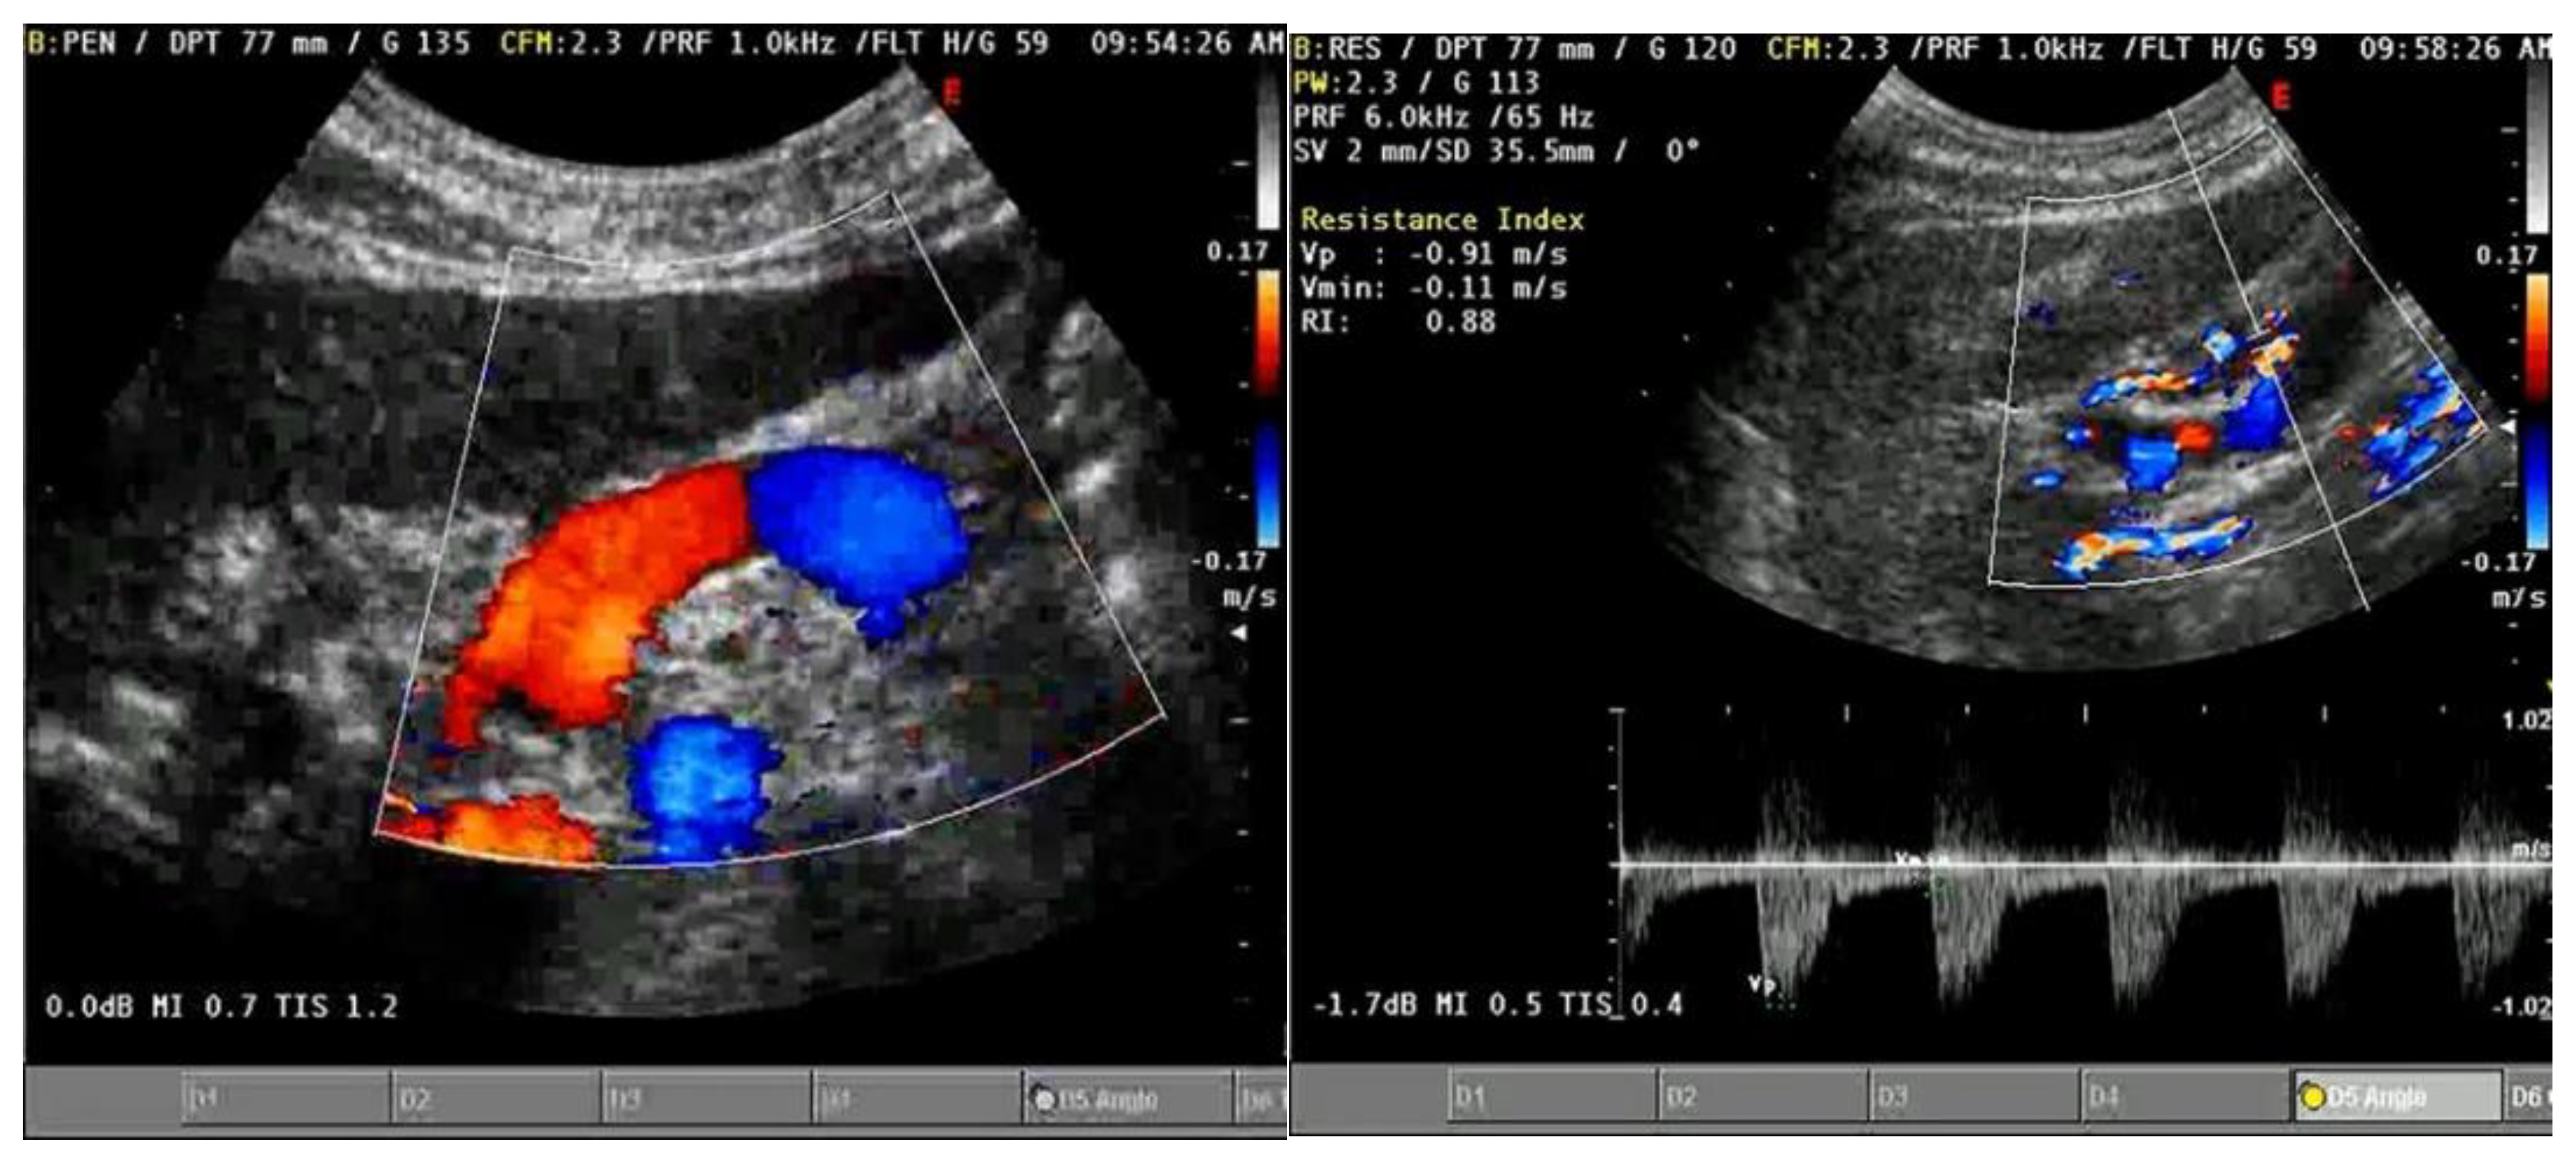

| Intrarenal venous | Aids in the assessment of | Simultaneous arterial Doppler allows | Technically challenging (especially when |

| Doppler | systemic venous | identification of cardiac cycle; exhibits | patients unable to hold breath); |

| congestion | dynamic change in response to | operator variability (e.g., misinterpret | |

| decongestive treatment | pulsatility of main renal vessel as renal | ||

| parenchymal vessel); change in | |||

| response to decongestive treatment | |||

| may be delayed in the presence of | |||

| interstitial edema; no available data for | |||

| patients with advanced chronic kidney | |||

| disease | |||